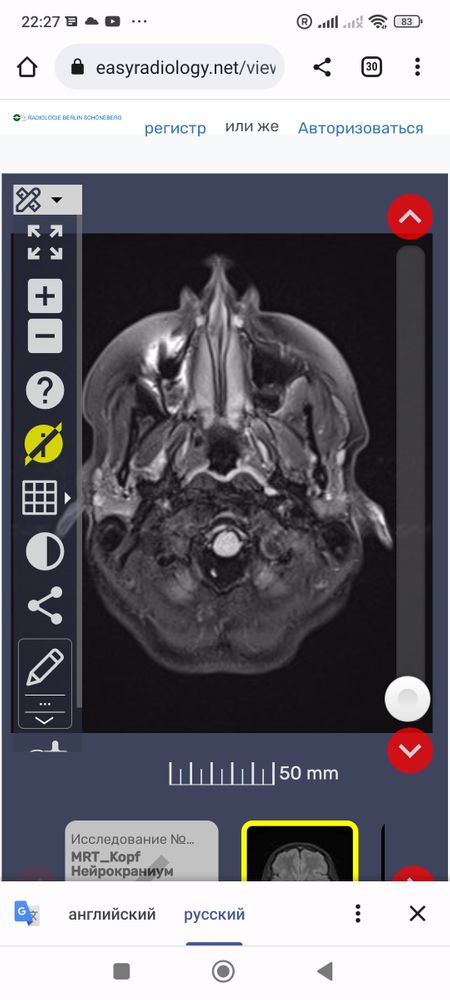

Что это за белые точки вокруг мозга? И все ли впорядке